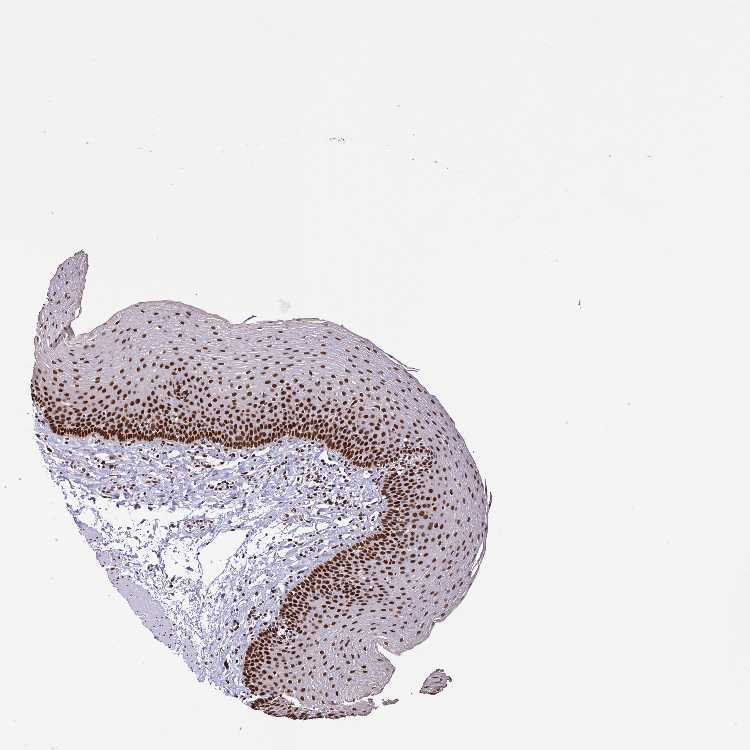

TISSUE PRIMARY DATA ESOPHAGUS Show tissue menu

ESOPHAGUS - Antibody stainingi

Antibody staining in the annotated cell types in the current human tissue is reported as not detected, low, medium, or high, based on conventional immunohistochemistry profiling in selected tissues. This score is based on the combination of the staining intensity and fraction of stained cells.

Each image is clickable and will lead to virtual microscopy that enables deeper exploration of all samples and also displays staining intensity scores, fraction scores and subcellular localization as well as patient and tissue information for each sample.

Antibody HPA064033Antibody CAB010066

Squamous epithelial cells HighLow